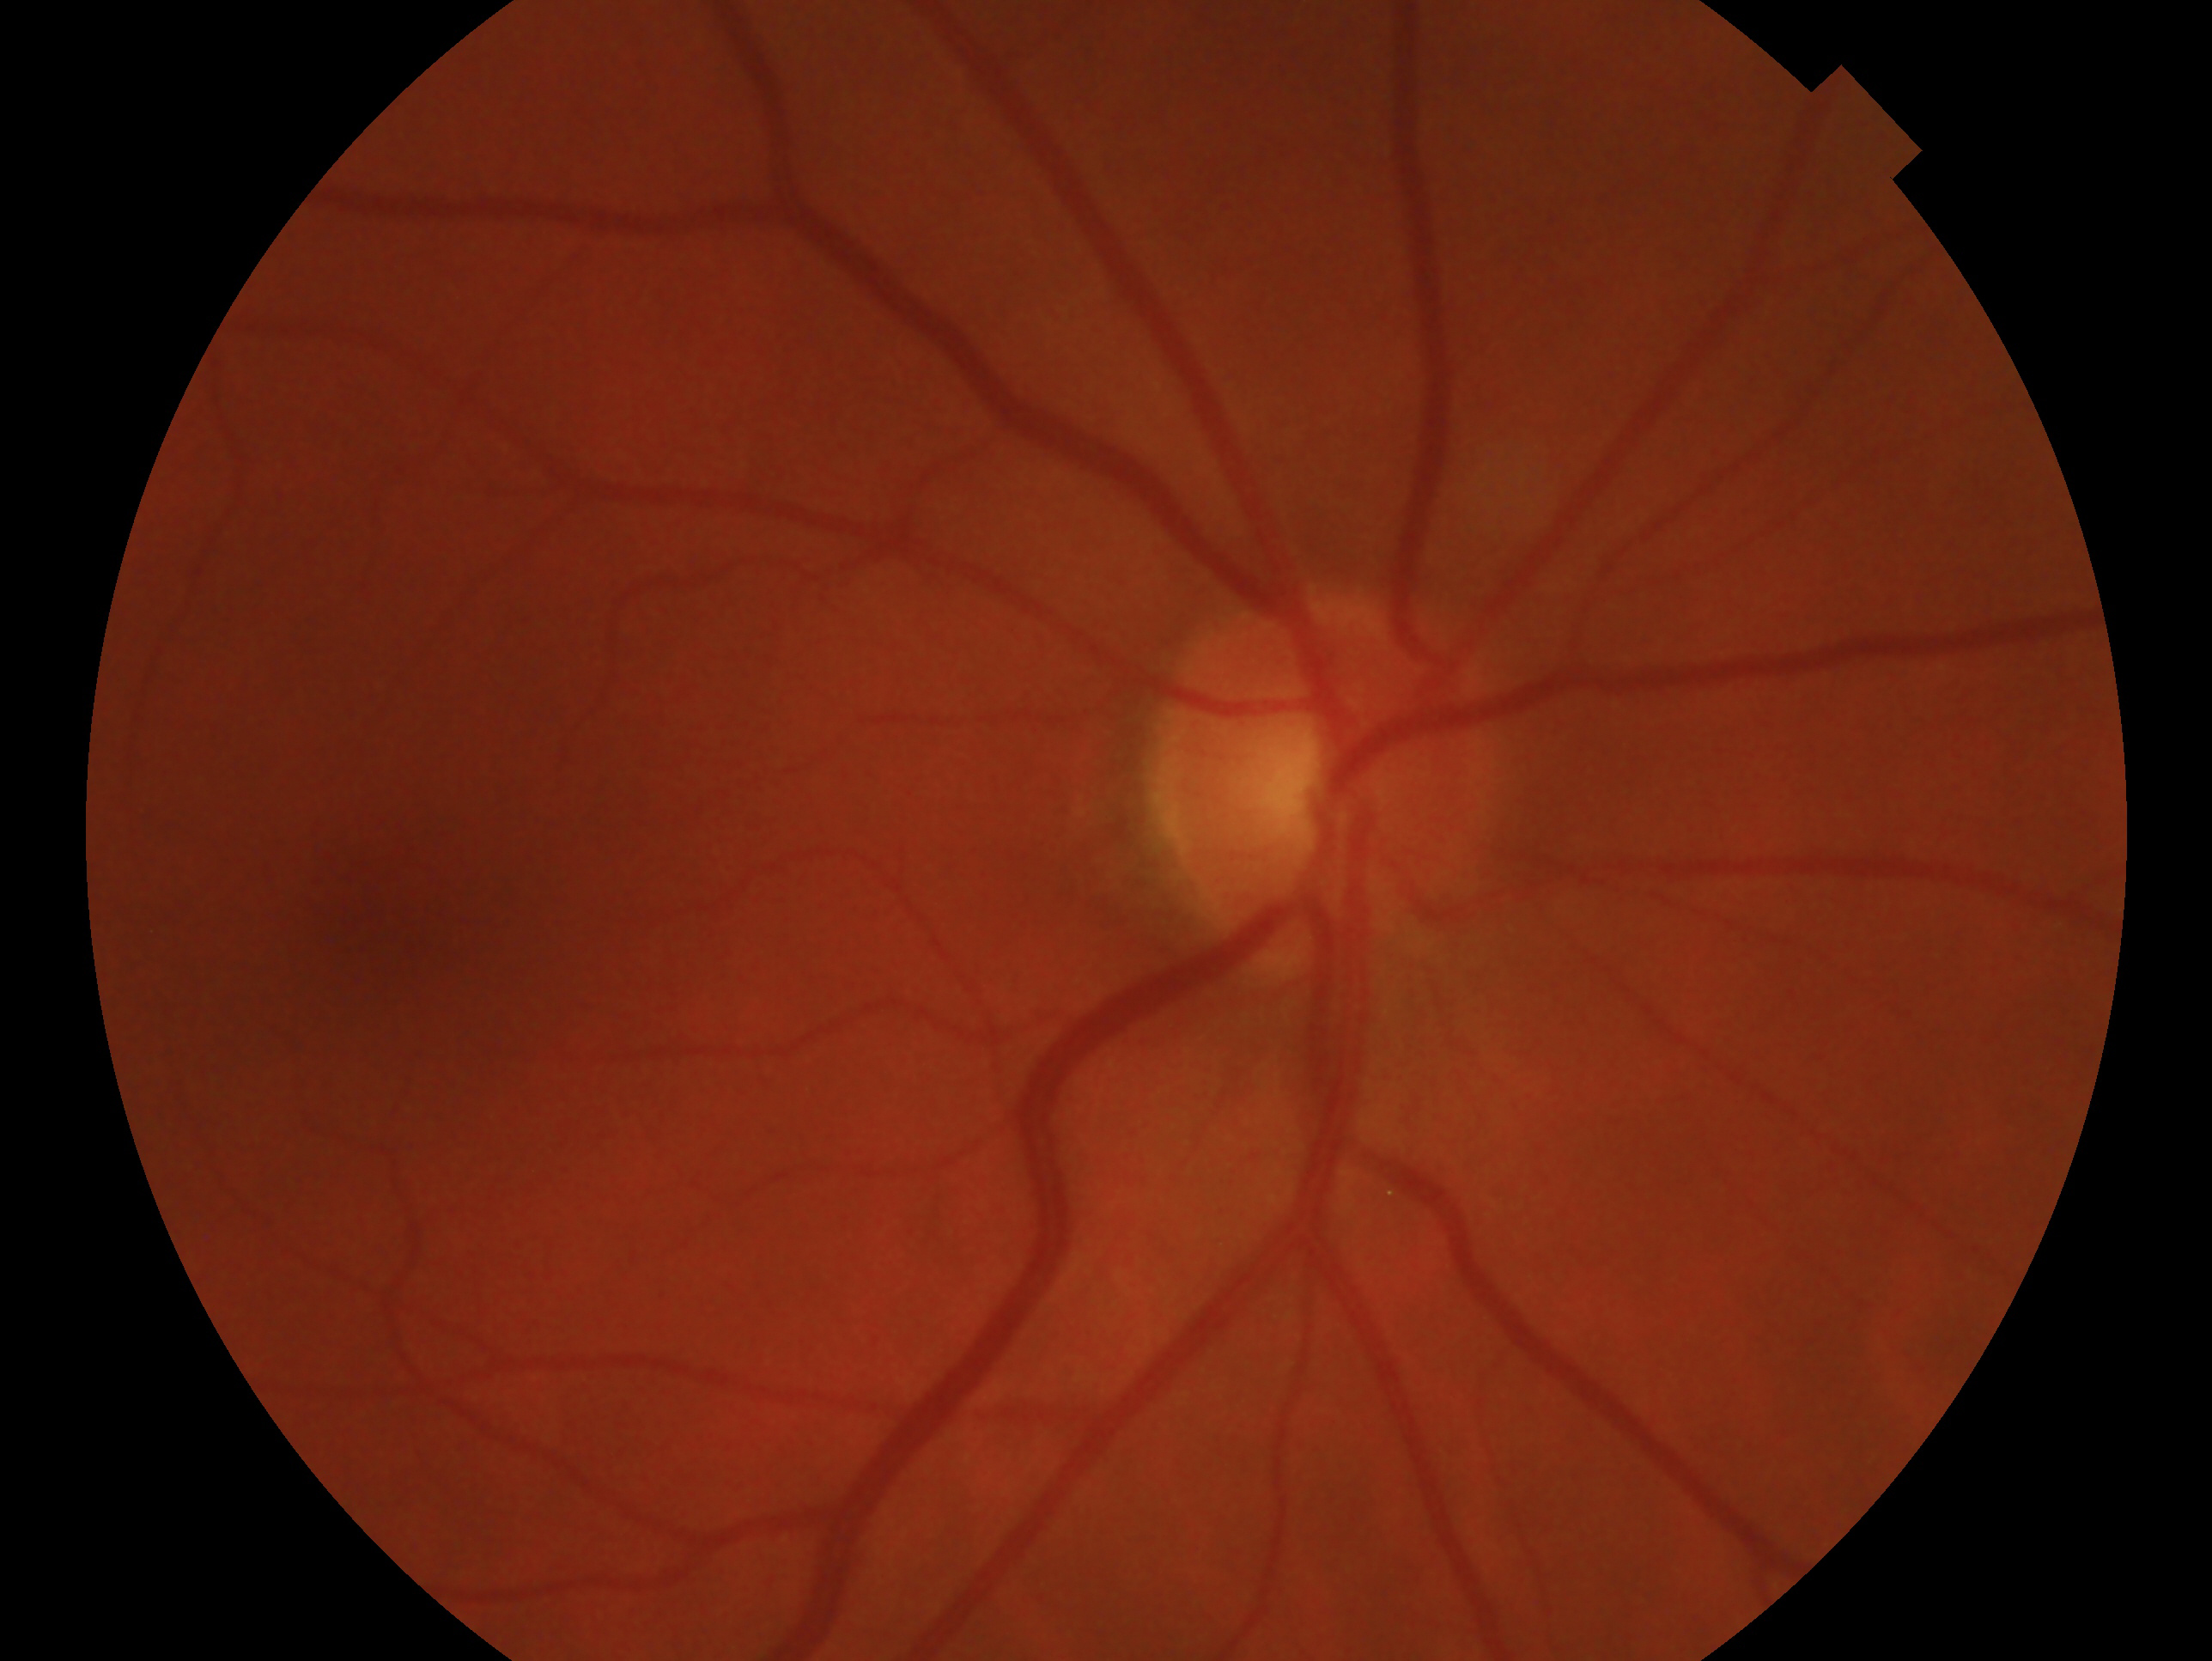

The PAPILA dataset [11] is a glaucoma classification dataset consisting of patient fundus images, along with their sex and ages. 364 patients are randomly chosen as the test set, including 118 male and 246 female patients, with 146 young (age 60) patients, and 218 elder (age 60) patients. The images are binary-labeled, indicating the diagnosis of glaucoma. The HAM10000 dataset [21] is a large-scale skin lesion classification dataset, consisting of dermatoscopic images of pigmented skin lesions, along with the patients’ sex and ages. 1,062 patients are randomly chosen for the test set, including 566 male and 496 female patients, with 472 young patients and 590 elder patients. A binary label indicates the diagnosis as malignant or benign. The MIMIC-CXR dataset [10] is large-scale dataset of chest radiographs with structured labels. 1,062 randomly chosen patients make up the test set, including 547 male and 488 female patients, with 439 young patients and 623 elder patients. A binary label indicates the diagnosis of pleural effusion. All experiments are conducted using GPT-4o-mini. Human review of input data is disabled on Azure OpenAI Service to comply with PhysioNet’s guidelines for responsible use of MIMIC-CXR with GPT [17]. We treat both sex and age as sensitive attributes. In each context, 4 additional patients are randomly selected from the dataset, apart from the test set, to serve as few-shot exemplars.